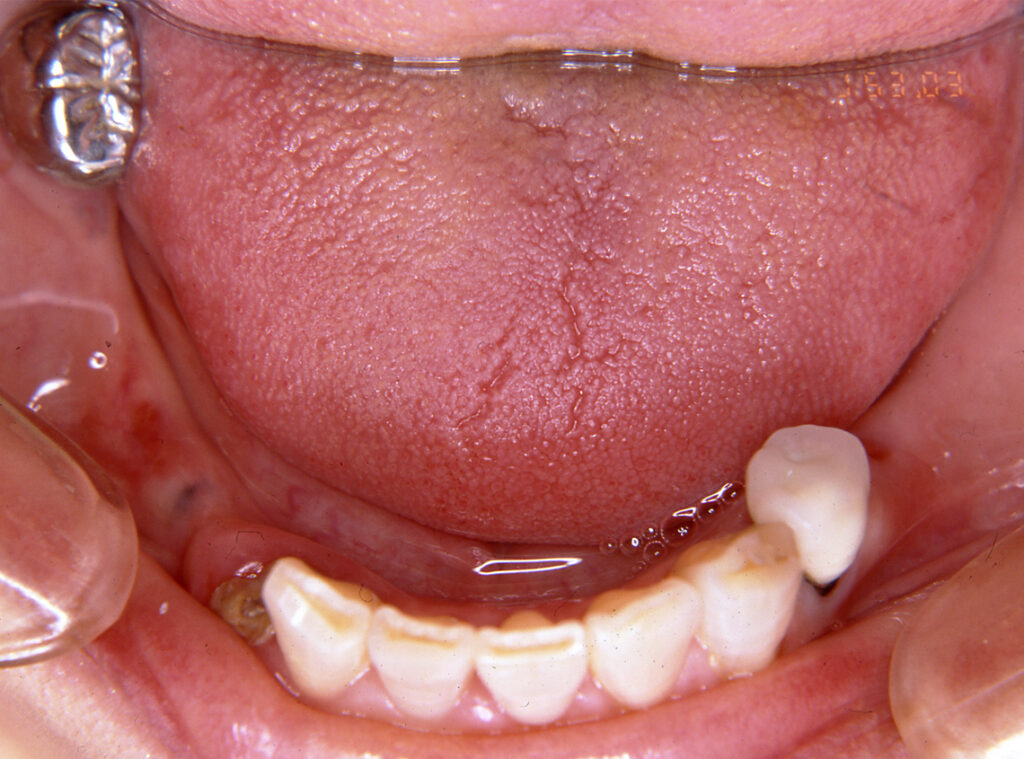

フルマウス治療17年間経過症例

患 者 : S.K様 女性

主 訴 : 補綴物破損、義歯不適による咀嚼障害のためインプラント治療希望

初診日 : 2003年07月11日

1.初診時(2003年)

3.治療中の仮歯(2007年)

インプラント埋入終了